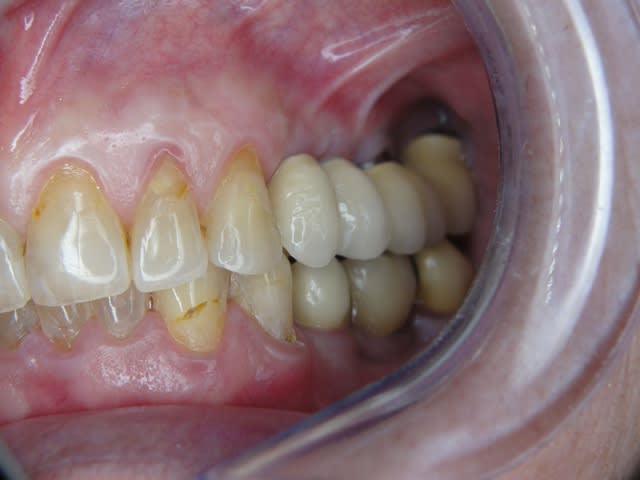

Pour ceux que ca interessent, et parce qu on a m a demandé des cas supplémentaires dans le sujet 23 implants rehabilitation totale, voici un autre cas d implantation immédiate avec la technique minimalement invasive et condensation grace aux forets.

Le patient a reçu un traitement il y a dix ans dans le maxillaire et dans le 4eme quadrant.Comme on peut le voir j´ai du extraire quelques dents au maxillaire: 35 37 et 45.

Le septum de la 37 a été foré avec un foret conique 3 faces.

J ai planté à 60 Ncm sans fracturer le septum.Juste après l opération , les prep caps en zircon ont été cémenté.La restauration définitive 34 jusqu` à 37 été fixé 2 semaines après l implantation avec implantlink (detax). Après un an, le bridge a été retiré facilement pour voir l´état de la gencive et faire une radio de contrôle.On la re ossifiction est satisfaisante et que la gencive "aime" le zircon.

Le bridge a ensuite été recémenté sans correction nécessaire du bridge.